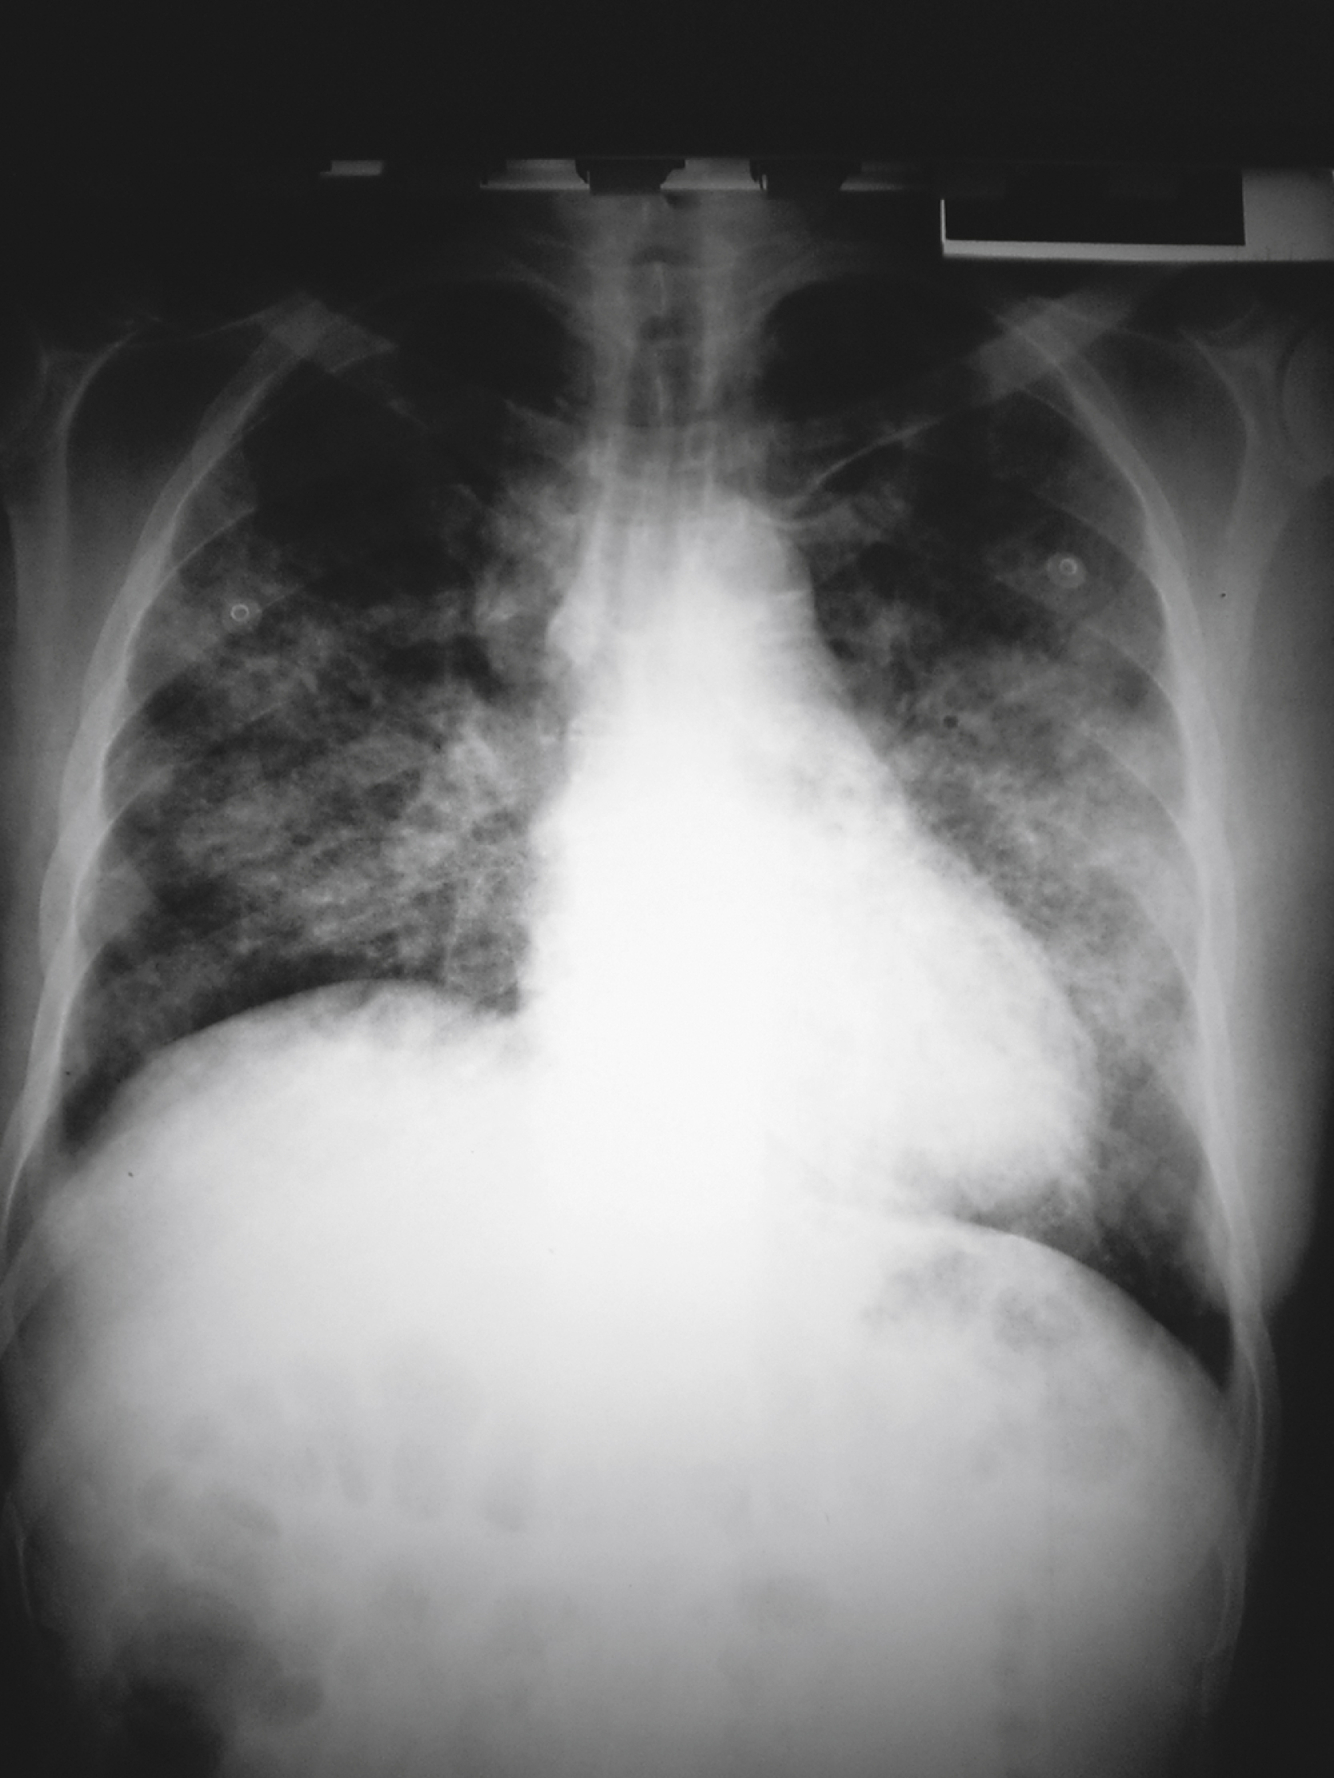

List 3 bacterial DDx for this CXR

A

• Streptococcus pneumoniae

• Haemophilus influenzae

• gram-negative bacilli